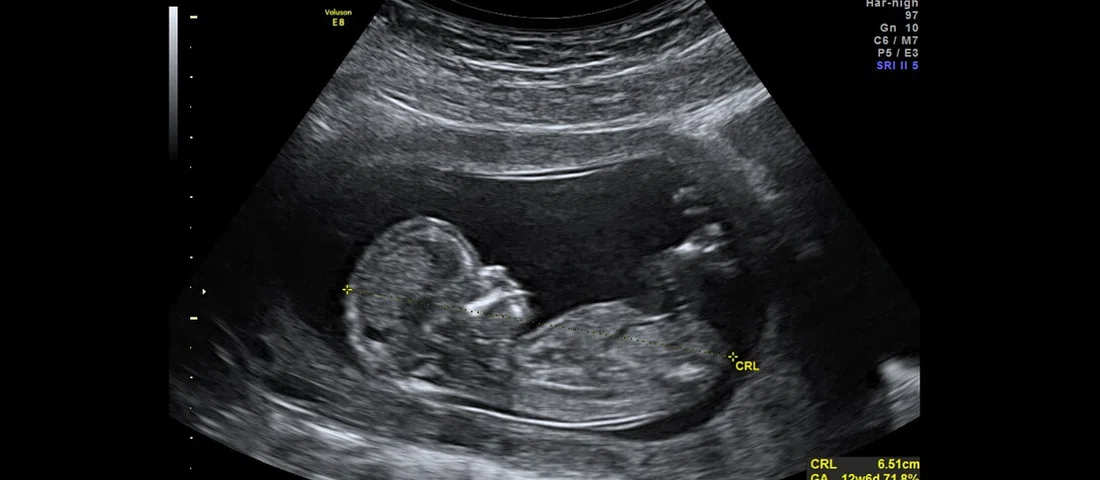

اودد وانونو، سرپرست تحقیقات شرکت چکپوینت در زمینه آسیبپذیریها، با یک بیمارستان در تلآویو روی سیستم اولتراسوند کار میکند که ممکن است در آینده نزدیک در سراسر بیمارستانهای دنیا بهکار گرفته شود. او در مصاحبهای با رسانهها در کنفرانس RSA 2019 گفته است که طی آزمایشهایشان روی این سیستم، متوجه شدهاند که تنها با دو کلیک میتوان روی این سیستم تغییرات ایجاد کرد. از آنجایی که شبکه بیمارستانها و دستگاههای هوشمند متصل به این شبکهها، بهراحتی قابل شناسایی و در دسترس هستند، این مساله به راحتی، قابل انجام است.

در همین رابطه وانونو گفته است که نیازی به مهندسی معکوس سیستم اولتراسوند و استفاده از مهارتهای خاص برای هک دستگاه وجود نداشته و تنها بهواسطه استفاده از ویندوز ۲۰۰۰ روی این سیستم، عملیات هک با موفقیت انجام شده است. سیستم عاملی که به پایان عمر خود رسیده و دیگر توسط مایکروسافت بهروز نمیشود. به همین دلیل، تیم تحقیقاتی چکپوینت بهسادگی توانسته است با استفاده از یک آسیبپذیری قدیمی و شناخته شده در این سیستم، به هک آن دست بزند.